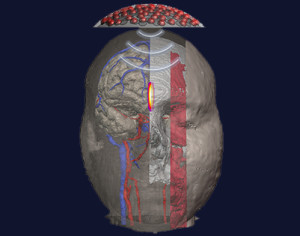

The activities of the research line Neuroscience and Society relate to the emerging field of social neuroscience, integrated with the original research concerning the neural representation of body image in healthy and brain-damaged patients, under the assumption that the body is the psychic object par excellence, at the core of many higher-order cognitive and social processes. In this scenario, one aim of the research topic is to investigate the possibility to stimulate specific neuronal areas in a safe and controlled manner. Among the widely used noninvasive brain stimulation techniques, focused ultrasound stimulation is an emerging technique for stimulating the brain more focally and deeply. Our purpose is to develop innovative ultrasound transducer configurations based on constructive beam interference methods, capable to reach deep brain structures without affecting the intervening ones.